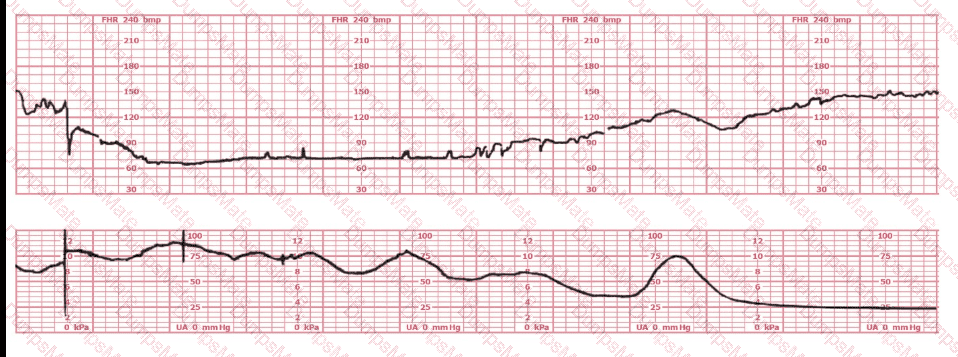

A woman at 41-weeks gestation is being induced. She is 2 cm dilated and is on oxytocin at 8 milliunits/minute. Based on the fetal heart rate tracing shown, the best initial response is to:

EFM Question 9

Options:

A.

Continue to observe

B.

Decrease the oxytocin

C.

Place a fetal spiral electrode